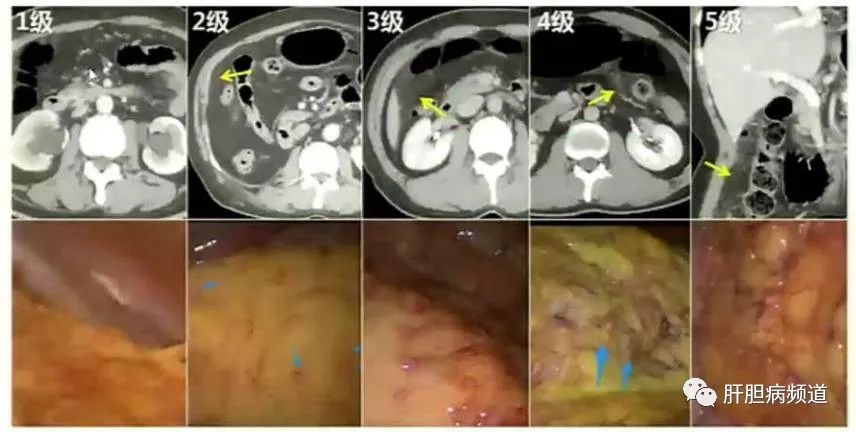

由于体内存在“血浆-腹膜屏障”,全身化疗时,分子量较大的化疗药物难以透过该屏障而作用于腹膜转移灶,并且全身化疗副反应重,效果不佳,患者往往因为严重的化疗反应而无法耐受,而腹腔内灌注化疗药物可延长药物在腹腔内的半衰期、提高局部药物浓度、减轻全身不良反应。其治疗方法包括诊断性腹腔镜检查、腹腔游离癌细胞检查、埋置腹腔化疗泵。可获得直视下腹膜转移和细胞学证据。故近年来出现了联合腹腔与全身性化疗的新辅助化疗。

现实腹腔化疗的主要方法是将化疗药物定期注入腹腔,而腹腔镜下置入埋藏式化疗泵,一是可以做到创伤小,二是可以在腔镜直视下取转移病灶行病理检查,明确恶性肿瘤腹膜转移的证据。埋藏式化疗泵是将输液管道经皮穿刺置于腹腔,并将注射硅胶头埋于腹壁皮下浅层,既方便注射给药,又不影响患者日常生活,优势明显。从而抑制腹膜转移灶和腹水形成、改善生活质量、延长生存期,可使部分患者病灶降期,有望施行根治术切除(R0切除),获得长期生存。